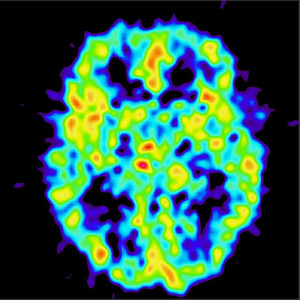

a head scan

According to the piece, scientists have discovered a way to connect with a patient who had been deemed unresponsive for twelve years. To do so, they used a brain-imaging machine.

In the study, three patients with severe brain injury who were considered non-responsive, one even vegetative, were able to show that they could follow commands by communicating with their attention: they had more brain activity when they were instructed to count than when they were relaxed.

This development could help researchers determine if a patient who seems unresponsive actually does have some consciousness and is essentially “trapped” in his or her own body.

Taking the study even further, two of the patients were able to focus their attention on specific questions, answering “yes” and “no” with their brain activity.